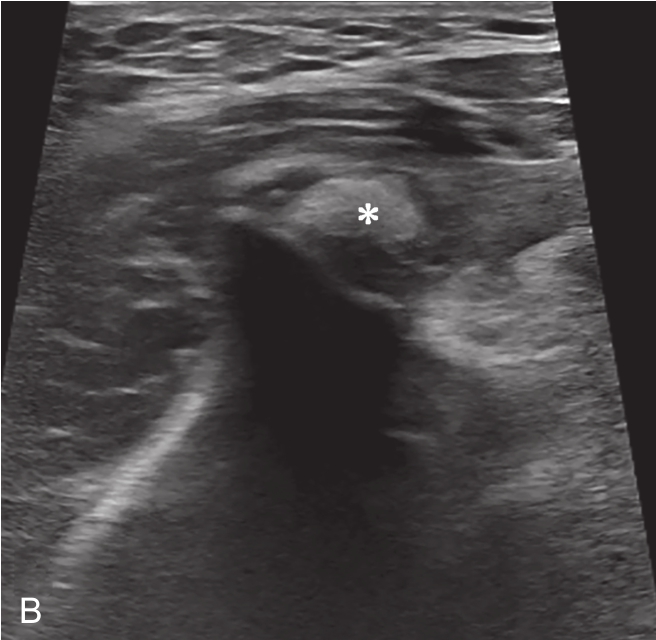

对物理治疗和口服药物治疗无效的钙化性肌腱炎,可行超声引导下钙化灶冲洗抽吸治疗,缓解疼痛和改善患者的活动功能。吸收期的钙化灶往往无明显声影,呈弱回声或稍强回声(图 2-2-1)。

▲ 图2-2-1 钙化性肌腱炎超声图

星号:钙化灶;箭头:肩峰下-三角肌下滑囊;Del:三角肌;SUP:冈上肌腱;HH:肱骨头